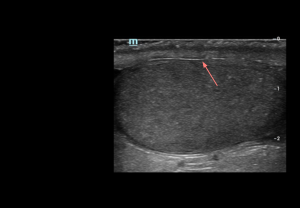

The testes, suspended in the scrotum, are ovoid and obliquely oriented, with the left usually slightly lower. On ultrasound, adult testes measure 3–5 cm in length, 2–4 cm in width, ~3 cm anteroposteriorly, with an average volume of 15–20 mL.

- Grey-scale: adult testes show homogeneous, medium-level echotexture with smooth, well-defined margins.

- Grey-scale: appears as a thin, continuous echogenic line demarcating the testis. Intact tunica albuginea is a key imaging feature in the assessment of scrotal trauma.

Mediastinum testis

- Grey-scale: appears as a linear or band-like hyperechoic structure along the longitudinal axis of the testis.